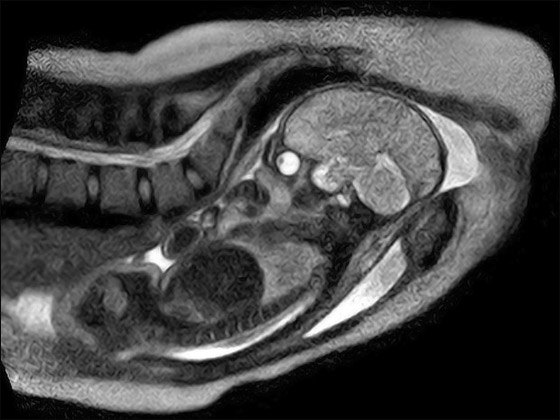

في الماضي لم يتمكن الأطباء في استخدام أشعة الرنين المغناطيسي لتصوير عملية ولادة بشكل كامل، لكن لحسن الحظ ولأول مرة في العالم، نجح أطباء بمستشفى شاريتيه الجامعي في برلين في استخدام أشعة الرنين المغناطيسي لتصوير عملية ولادة بشكل كامل.

كانت الأم موجودة طوال عملية الولادة داخل جهاز مفتوح لأشعة الرنين المغناطيسي، مما أعطاها نوعا من حرية الحركة وسمح للمشاركين في عملية التوليد بالاقتراب منها وتوليدها. وعن هذا السبق، قال البروفيسور ارنست بايندر، أستاذ طب النساء والولادة: "كانت ولادة نموذجية رأينا من خلال تصويرها تفاصيل لم نكن نعلمها إلا من خلال الفحص باللمس".

يأمل الأطباء من خلال توثيق عمليات الولادة في التعرف مبكرا على المراحل الحرجة للولادة وتقديرها بشكل أفضل لتحسين طريقة التعامل معها، وحتى لا تتعرض الأم لأشعة ضارة بسبب جهاز الرنين المغناطيسي.